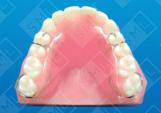

Interim Partials and Bridges

Temporary or interim appliances serve many useful purposes. Indicated when age, health, poor finances, or lack of time precludes a more definitive treatment, and can often constitute an integral part of a prosthetic treatment plan.

An interim appliance is often used in young patients who, because of an accident, rampant caries, or hereditary partial anodontia, are missing either anterior or posterior teeth. Because permanent restorations are usually contraindicated for some time in a growing child, interim partials and bridges are an excellent method of choice for maintaining the patient’s esthetics and function. Elderly patients whose health contraindicates the lengthy and grueling appointments required to construct permanent fixed replacements for missing teeth are excellent candidates for interim restorations. These patients can usually tolerate the simple clinical procedures needed to construct and insert a temporary appliance. For those patients who have suffered a financial setback, cost of an interim partial or bridge is considerably less than that of the definitive treatment eventually required -- and as such, far more likely to be selected.